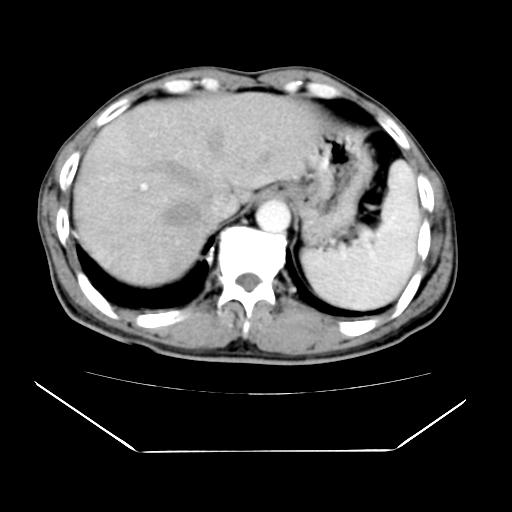

男性,55岁,外院体检afp明显升高,但b超未发现异常,否认乙肝病史。来我院ct增强。有延时扫描。

延时扫描完全充填,血管瘤

肝脏右叶动脉期可见低密度影,至延迟期被充填,考虑血管瘤可能性大。

不排除肝右叶肝癌可能。

如果这个是癌灶的话则下腔静脉有瘤栓可能

肝6段血管瘤

血管瘤可能性大。

考虑肝右静脉影。